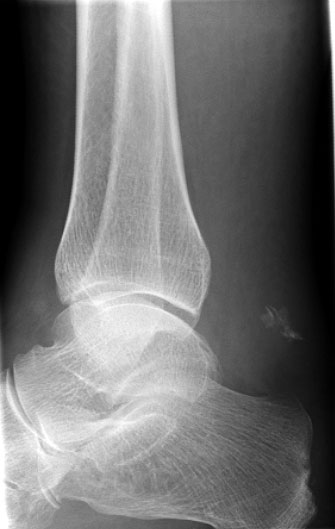

Knöcherne Ausrisse lassen sich in der seitlichen Röntgenaufnahme des Sprunggelenkes ausschließen oder beweisen (Abb. 5). Eine Sonderform bilden hier die Entenschnabelfrakturen des Kalkaneus.

Abbildung 5

Der geübte Untersucher kann anhand des seitlichen Röntgenbildes die Diagnose einer Achillessehnenruptur stellen. Die Konturen des Kager-Dreiecks – gebildet von der ventralen Begrenzung der Achillessehne, der posterioren Tibiakante und der kranialen Kalkaneuskortikalis – verstreichen im Rupturfall (Kager 1939). Die MRT- Diagnostik spielt für die Primärdiagnostik der frischen Achillessehnenruptur eine untergeordnete Rolle und ist im Normalfall nicht notwendig. Anders verhält es sich bei den chronischen Rupturen. Hier ist die MRT ein wichtiges Diagnostikum insbesondere in Hinblick auf die Beurteilung der Sehnen- und Muskeldegeneration (Abb. 6).